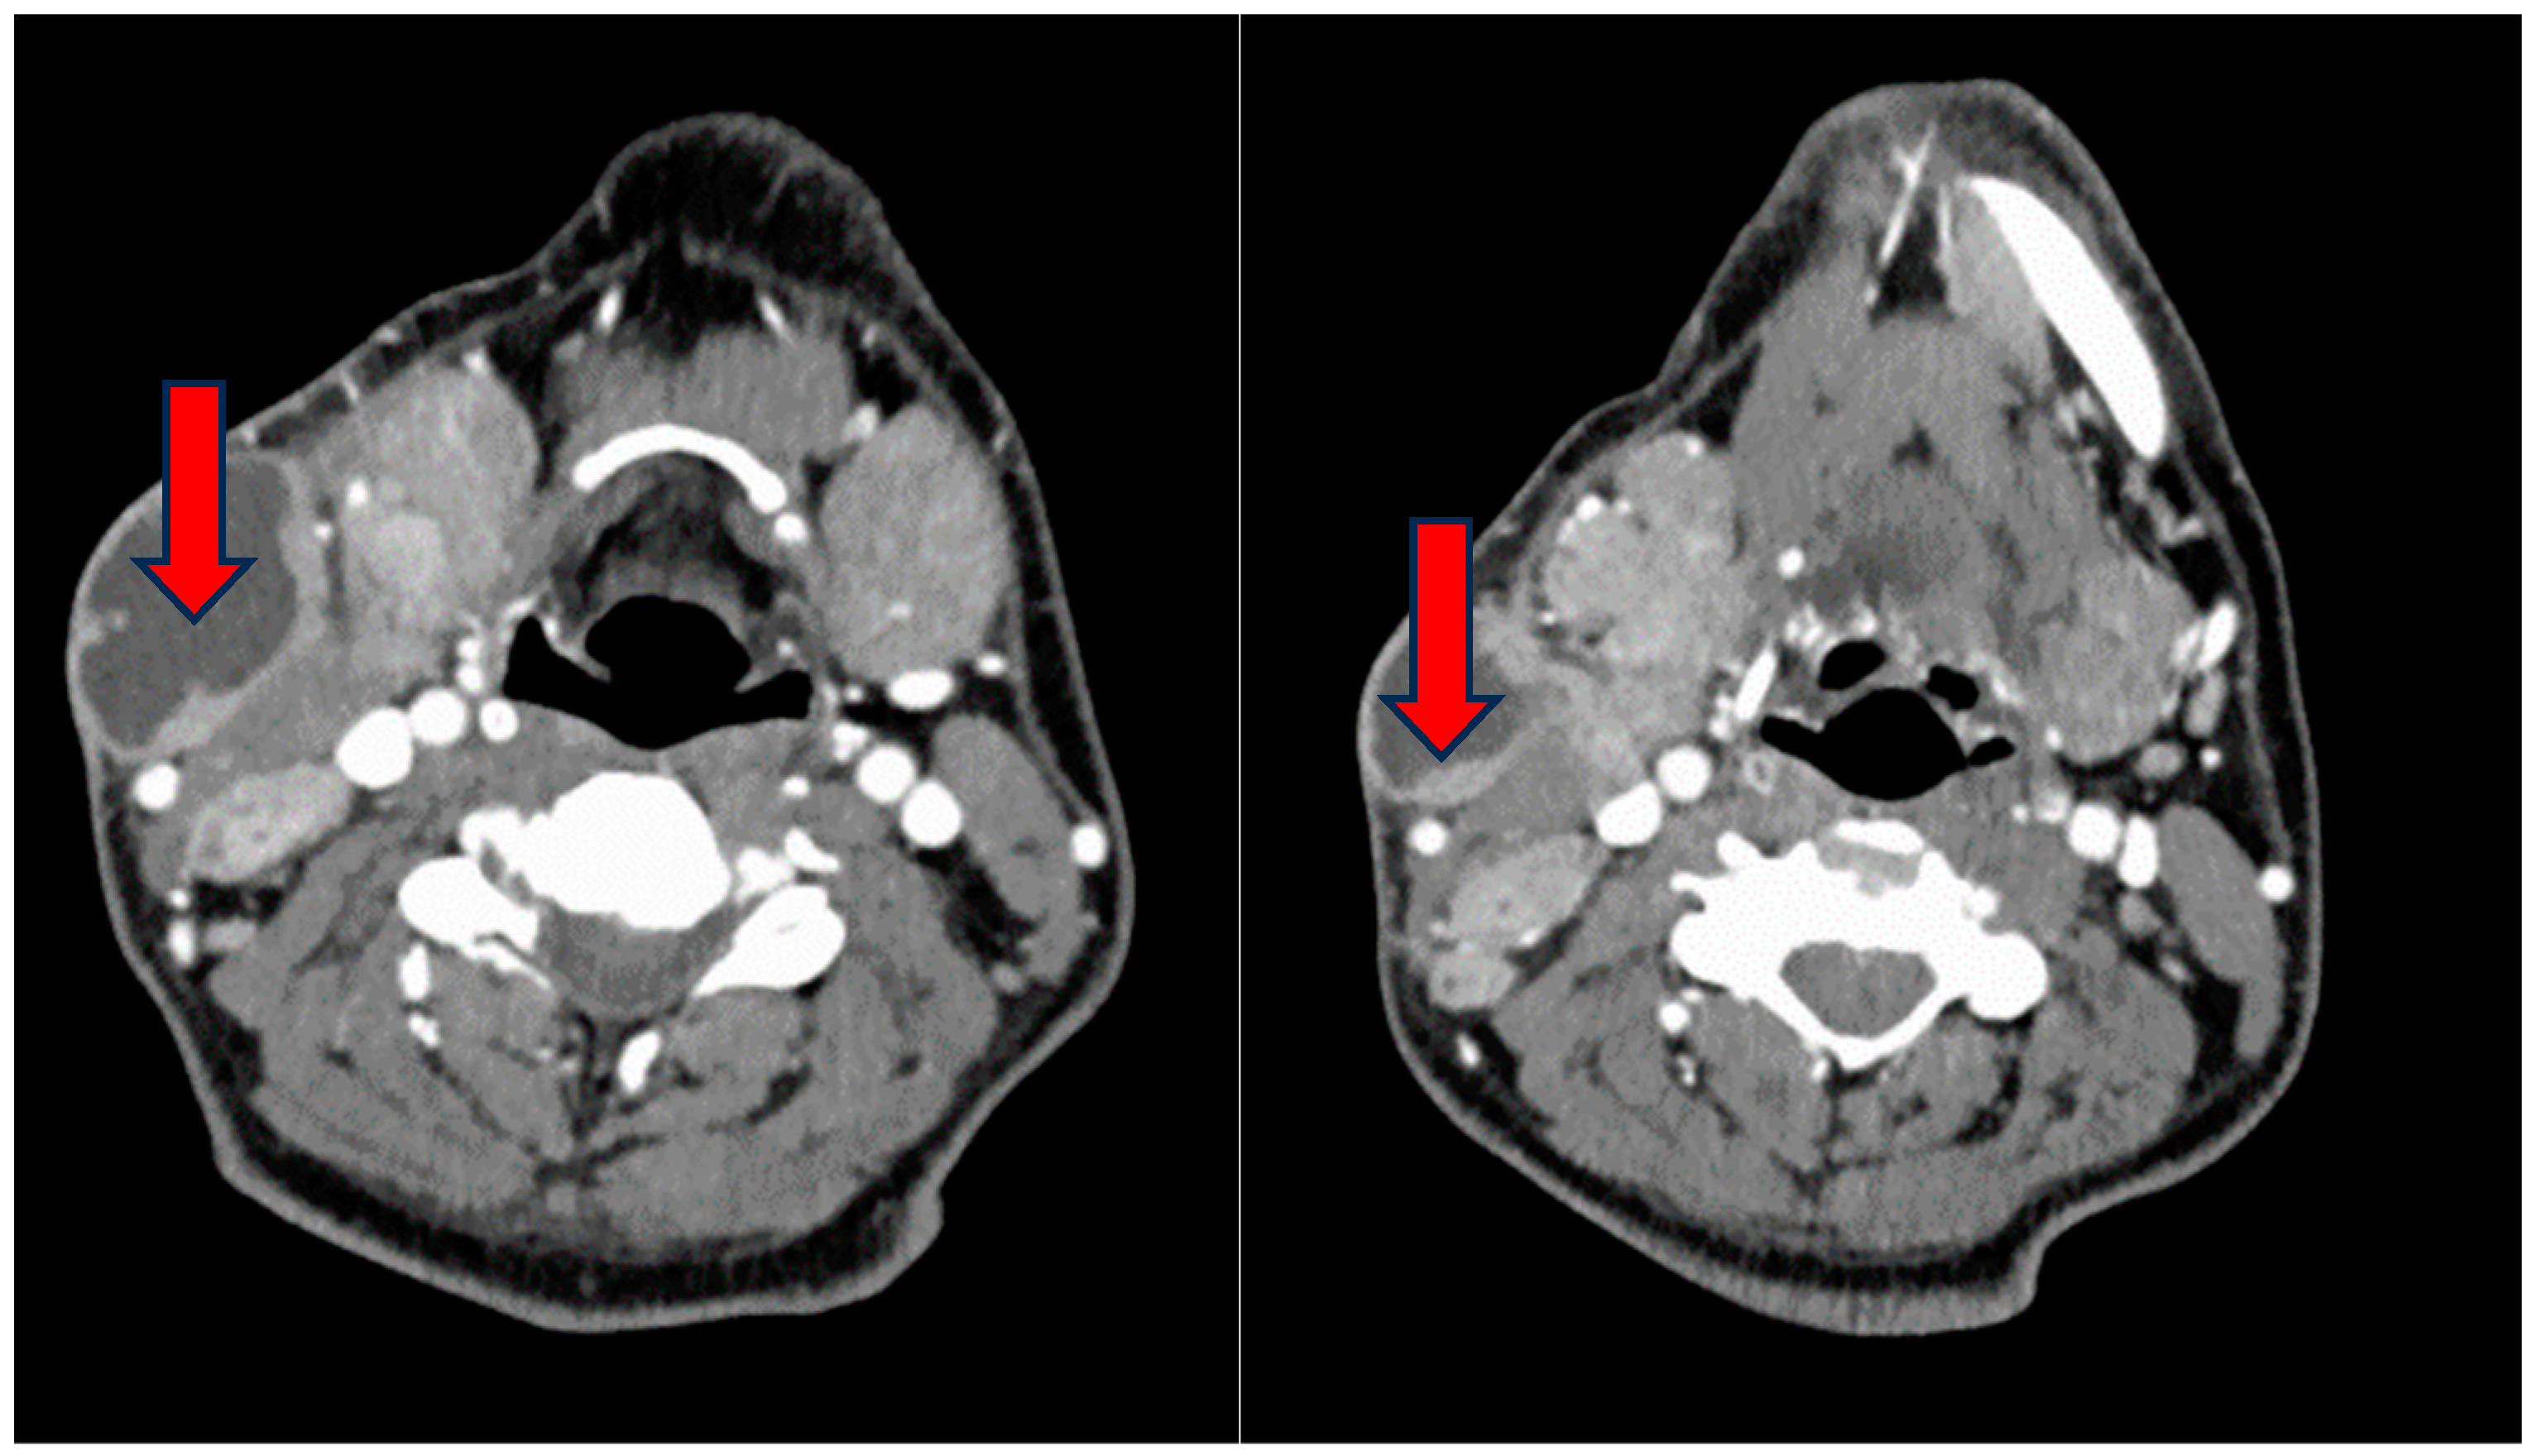

2. Case Presentation